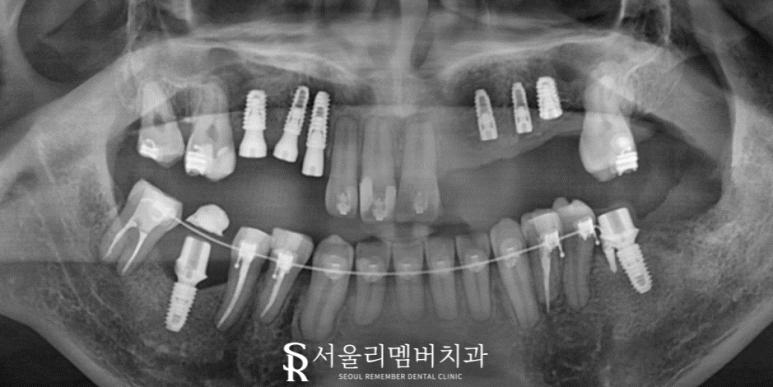

출처 아카이브 열기오늘은 심한 충치와 삐뚠 배열로 몇 년 전 저를 찾아오셨던 환자의 회복 과정을 소개해 드리려 합니다.

제가 여태껏 진료 했던 분들 중 충치가 제일 심하다고 해도 과언이 아닐 만큼 구강 상태가 좋지 않았는데요.

그래서 그런지 아직까지도 생생하게 기억이 나는 분이죠.

남성역 치과 와 함께 살펴보며 자세히 설명드리겠습니다.

정면 사진을 딱 보면 어떤 문제들이 관찰되실까요?

이미 상할 만큼 상해버린 잇몸과 심하게 진행된 충치, 그리고 곳곳에 깨져있는 치아까지..

그야말로 정말 심각한 구강을 갖고 계셨습니다.

이와 더불어 어금니 배열이 밑으로 꺼져 있고, 위로 올라가 있는 등 교합에 있어서도 큰 문제가 있었는데요.

교합면에서 좀 더 자세히 관찰할 수 있었습니다.

빠져버린 이는 물론이며, 치관 대부분이 깨져 사라진 곳도 있었고 아예 형태를 잃은 이들도 눈에 보입니다.

이 정도라면 식사를 제대로 할 수도 없었을 텐데요.

식사뿐만 아니라 구취, 외관의 문제로 타인과의 의사소통도 힘드셨을 겁니다.

앞서 언급했듯이 배열의 문제도 빼놓을 수 없었는데요.

좌, 우측 대칭이 맞지 않기 때문에 보철치료를 한 뒤에도 제대로 맞물리지 않을 겁니다.

즉, 맞물리지 않으면 보철이나 치아의 형태 변형이 생기는 것을 물론이며,

빈 공간으로 이동하는 정출, 음식을 씹을 수 있는 저작 등이 아예 불가능하다는 뜻이죠.

음.. 이런 진단 내용을 토대로 남성역 치과 에서는 아래와 같은 계획을 세웠습니다.

우선은 살릴 수 있는 치아들은 남겨놓고 치과의 파절이 큰 곳이나 치근만 남아있는 곳들은 깨끗하게 제거했습니다.

이때 남성역 치과 에서는 방해가 될 수 있는 매복 사랑니도 함께 뽑아주었습니다.

신경치료로 살릴 수 있는 치아들은 감염된 근관을 제거해 주고 소독, 충전의 과정을 거쳐 회복을 도왔습니다.

교정이 진행되고 있는 동시에 픽스쳐를 식립했습니다.

총 8개의 픽스쳐 식립을 마무리 지었네요ㅎㅎ